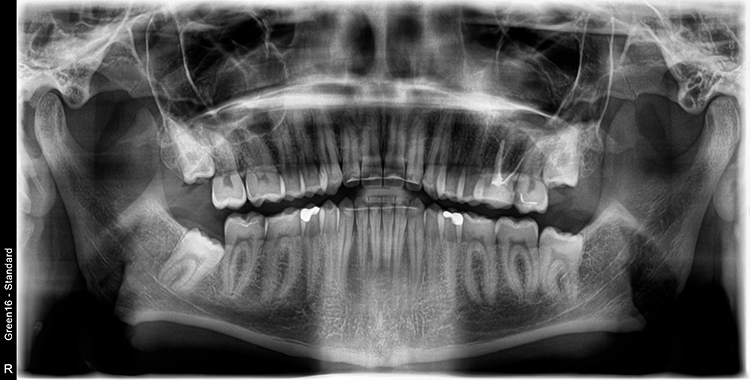

Abb. 2: Repräsentativer Fall von ABH Grad B Septus Typ II. a) Ansichten vor der Installation. Röntgenaufnahme der periapikalen Läsion an einem wurzelkanalbehandelten Molaren und klinische Ansicht der Typ-II-Socket nach der Extraktion. b) Die Ansichten nach der Installation zeigen das Implantat innerhalb des interradikulären Septums und das über dem Implantat platzierte A-PRF. c) Nachuntersuchungen nach 10 Tagen bzw. 2,1 Monaten. Die Röntgenaufnahme zeigt die Knochenbildung zwischen der Sinusmembran und dem apikalen Teil des Implantats. d) Jüngste Nachuntersuchung nach Einsetzen der Prothese.

Abb. 3: Repräsentativer Fall von Grad A Typ I. a) Präoperative Ansicht. Röntgenbild der periapikalen Läsion an einem wurzelkanalbehandelten Molaren. Die Höhe des Alveolarknochens zeigt Grad A an. b) Klinische und radiographische Ansicht der Implantatinsertion unter Verwendung einer Einheilscheibe mit großem Durchmesser (6×8 mm). A-PRF wurde um das Implantat und unter der Scheibe platziert. c) Nachuntersuchung nach 5,9 Monaten vor und nach der Zementierung und Aufbereitung. d) Jüngste Nachuntersuchung nach Einsetzen der Prothese

Abb. 4: Repräsentativer Fall von Grad A Typ III. a) Ansichten vor der Implantation. Röntgenbild der periapikalen Läsion an einem wurzelkanalbehandelten Molaren. b) Die Extraktionsalveole zeigt ein interradikuläres Septum vom Typ III (B).

Bei dem balkonförmigen Implantat blieben die Alveolarkämme und der Kronenansatz erhalten (Abb. 4c und d). Der Spalt zwischen dem Implantat und der bukkalen Lamelle wurde mit A-PRF und einem Kollagenblock aufgefüllt, so dass keine zusätzliche Knochenaugmentation erforderlich war. Zusätzlich wurden PRF-Matrizen um, über, unter und neben dem Implantat im Knochen-Implantat-Raum positioniert (Abb. 1 bis 4b). Außerdem kam eine optionale Einheilscheibe (6 x 8 mm) zum Einsatz, um das Kollagen und die PRF zu sichern (Abb. 3b). Die Implantate zeigten bei einem Drehmoment von 35 Ncm Stabilität, welche mit dem Periotest-Gerät von Medizintechnik Gulden getestet wurde. Die Werte des Implantatstabilitätstests, die im Bereich von –8 bis 0 lagen, wurden als ideal für die Belastung angesehen (Tab. 3).

Querschnittsbilder aus dem DVT zeigen eine hohe Genauigkeit und Zuverlässigkeit bei linearen Knochenmessungen im Zusammenhang mit der Implantatbehandlung [2]. Marginale Knochenniveaus wurden am Schnittpunkt zwischen der Längsachse des Implantats und der mesiodistalen Linie gemessen, die durch den größten krestalen Knochen auf jeder Seite des Implantats markiert ist und als Referenzpunkt für die Messung des Knochenverlusts bei Nachuntersuchungen dient. Trotz der begrenzten Anzahl von Implantaten und der Beschränkungen der Studie wurde eine Überlebensrate von 100% erreicht.